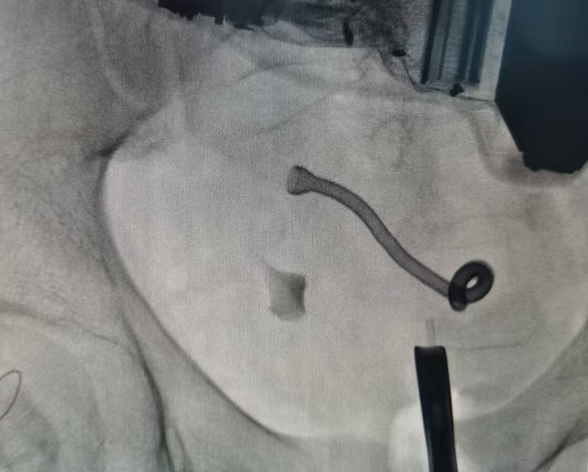

患者因肾移植术后输尿管狭窄,长期遭受移植肾积水和肌酐异常的困扰,严重影响了生活质量。传统的治疗方案往往需要定期更换输尿管支架管,给患者带来了极大的不便和痛苦。此次手术采用的“温控记忆合金支架”是一种新型的医疗器械,具有遇热膨胀、遇冷变软的特性,能够在狭窄部位提供持久而稳定的支撑。手术过程中,移植泌尿外科团队精确放置了金属支架,在注入规定温度热水后,金属支架成功膨胀并锚定于狭窄处,使尿道恢复通畅,手术圆满完成。术后,患者移植肾积水症状即刻明显缓解,生活质量将得到极大地提升。